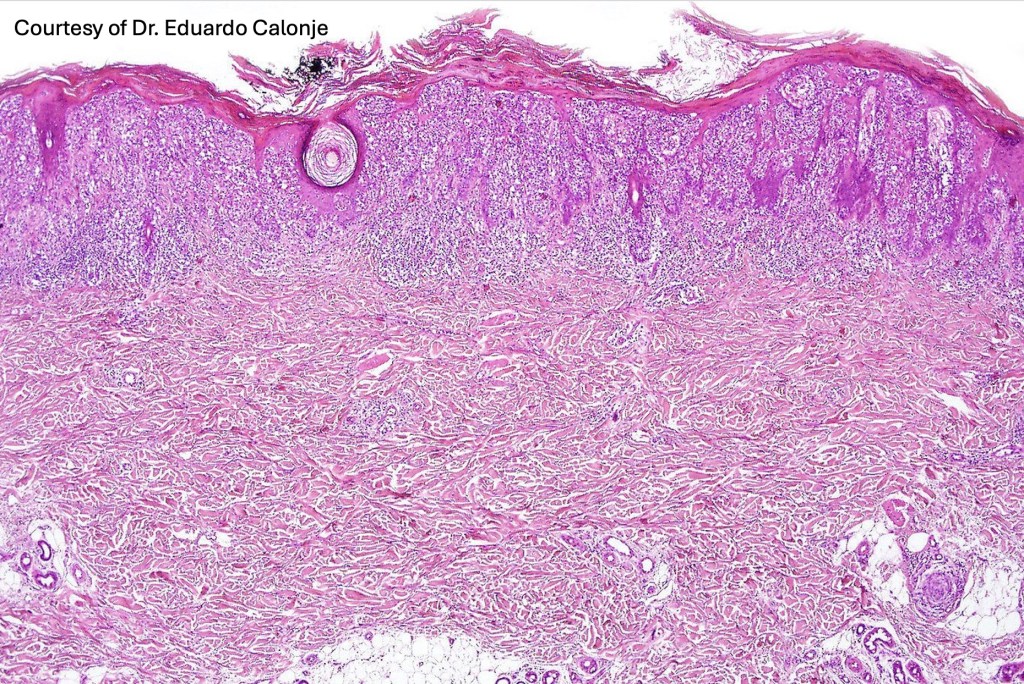

Histological features

•Hyperkeratosis/parakeratosis

•Acanthosis often psoriasiform

•Very marked epidermotropic infiltrate of atypical lymphocytes including Sézary cells

•Pautrier-like microabscesses

•Superficial dermal perivascular lymphohistiocytic infiltrate with only sparse or absent atypical forms